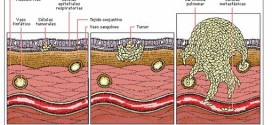

El tumor vesical macroscópicamente (masa extravesical) (T3B). Durante los primeros años de vida de una persona, las células normales se dividen más rápidamente para permitir el crecimiento. El cuerpo está compuesto por billones de células vivas. Las células normales del cuerpo crecen, se dividen formando nuevas células y mueren de manera ordenada. Una vez que se llega a la edad …

El tumor vesical microscópicamente (T3a). Tumor maligno en general. La orina es un líquido formado por agua y sustancias de desecho del organismo. Esta se produce por el filtrado de la sangre en los riñones. A través de unos tubos largos y finos, denominados uréteres, la orina llega a la vejiga y se almacena en ella. La orina, una vez …

El tumor vesical que invade (próstata, útero o vagina (T4a). Tumor maligno en general. Publicado en: binipatia.com Escrito por: Salvador Gregori y Daniel Lynch Etiquetas: salud verdadera, resultados Resumiendo: La vejiga urinaria es un órgano hueco musculo membranoso que forma parte del tracto urinario y que recibe la orina de los uréteres y la expulsa a través de la uretra al exterior …